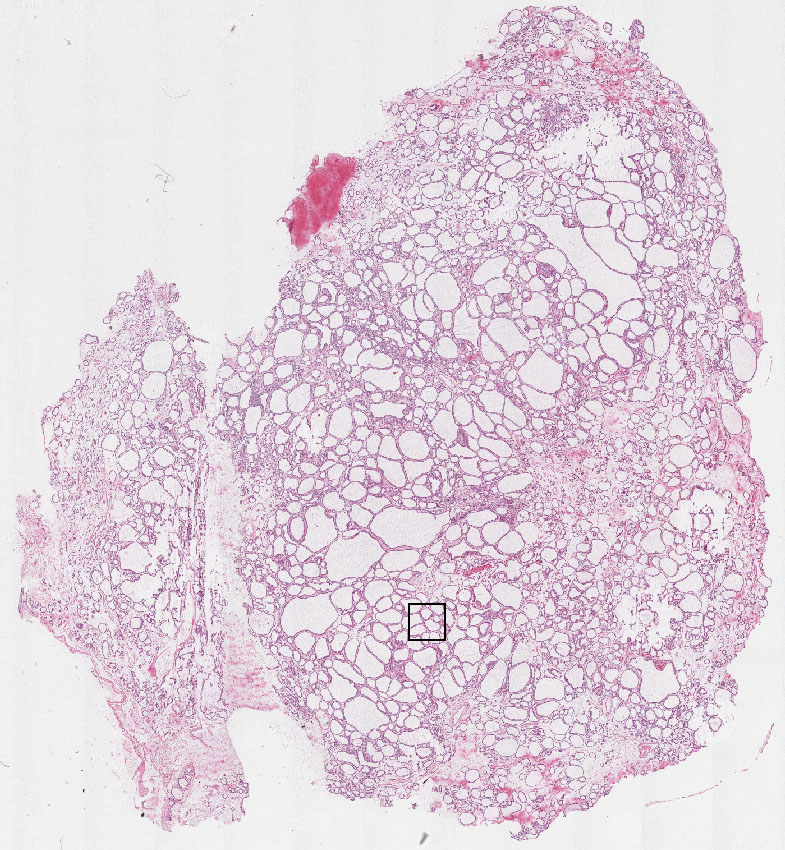

Cell types%

Glandular cells:

70

Endothelial cells:

20

Other cell types:

10